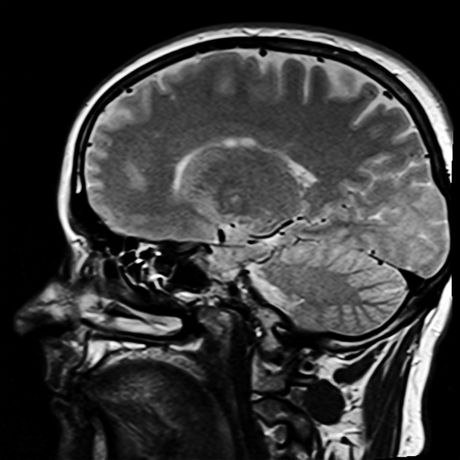

Stručnjaci odavno znaju za potencijalne rizike od potresa mozga među mladim sportistima, naročito kod onih koji igraju izrazito kontaktne sportove kao što su fudbal, hokej i ragbi. Sve je više dokaza da se ponovljeni udarci u glavu, čak i ako se isprva učine blagim, mogu akumulirati tokom više godina i dovesti do kognitivnog oštećenja. Iako napredni MRI identifikuje mikroskopske promene u strukturi mozga usled traume glave, istraživači kažu da snimci proizvode ogromnu količinu podataka kojom je teško upravljati.

Nova studija koju sprovode naučnici sa Odeljenja radiologije Medicinske škole Grosman Njujorškog univerziteta pokazala je prvi put da novi instrument, koji koristi AI tehniku zvanu mašinsko učenje, može precizno razlikovati mozgove sportista koji su igrali kontaktne sportove poput fudbala i onih koji se bave nekontaktnim sportovima poput atletike. Rezultati su povezali ponovljene udarce u glavu sa malim strukturalnim promenama u mozgovima kontaktnih sportista kojima nije dijagnostikovan potres mozga.

Istraživači su analizirali snimke magnetnom rezonancom kod 81 sportiste, napravljene 2016-2018, od kojih nijedan nije imao dijagnostikovan potres mozga u tom periodu.

Naučnici su naučili program da identifikuje neobična svojstva u moždanom tkivu i razlikuje sportiste sa i bez ponovljenog izlaganja povredama glave. Takođe su rangirali koliko je svako svojstvo korisno za detekciju oštećenja radi otkrivanja koji od brojnih MRI pokazatelja bi najviše mogao doprineti dijagnostikovanju.

„Naši rezultati ističu moć veštačke inteligencije da nam pomogne da vidimo stvari koje ranije nismo mogli da vidimo, naročito ’nevidljive povrede’ koje se ne prikazuju na konvencionalnim snimcima magnetnom rezonancom“, rekao je glavni autor studije Đuenbo Čen, doktorand Škole za inženjering na Njujorškom univerzitetu. „Ovaj metod će možda obezbediti značajno dijagnostičko sredstvo ne samo za potres mozga, već i za detekciju oštećenja koja proističu iz blažih i češćih udaraca u glavu“.